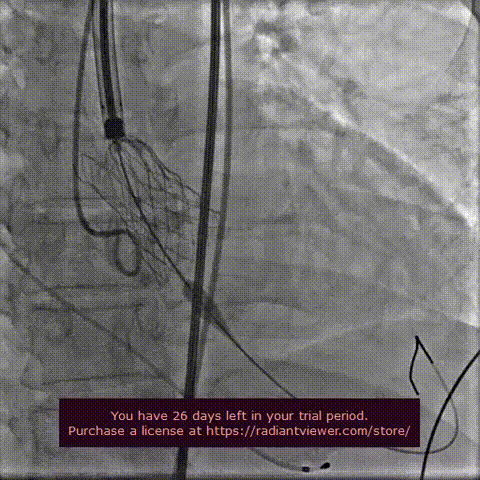

瓣膜释放前主动脉根部造影:

主动脉根部造影

球囊扩张 :22mm球囊预扩,无漏,冠脉灌注良好,冠脉风险可控。

球囊预扩张